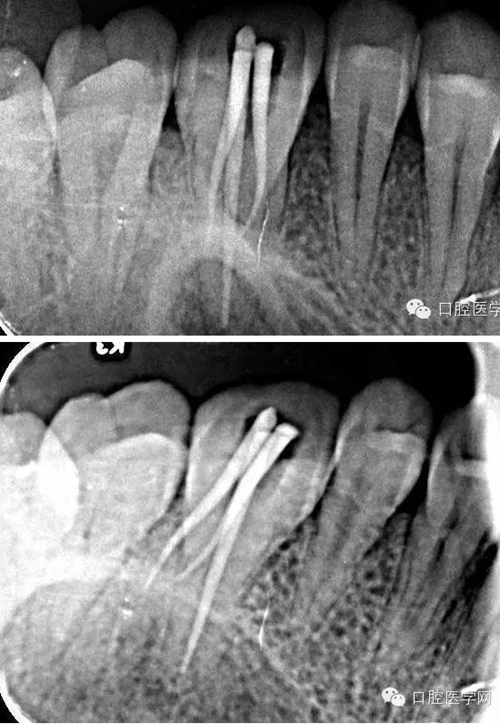

復(fù)診:原暫封材料在位,患牙無不適癥狀。去除原暫封材料,大量沖洗液沖洗根管,紙尖干燥根管,試尖合適,AH-plus糊劑+登士柏大錐度牙膠充填,光固化樹脂充填。拍術(shù)后片顯示充填良好,建議一周后全冠修復(fù),術(shù)后拆除牙齦縫合線,局部消毒。

術(shù)后x線片:

本病例治療過程中醫(yī)患配合良好,主要難度在患牙的確診與齦上潔治術(shù)后牙齦出血不止,患者依從性好,感謝患者的信任,S3鎳鈦器械的柔韌性強(qiáng),切削效率高,單一長度預(yù)備技術(shù)使操作簡單,獨(dú)特的預(yù)灣功能能自適應(yīng)根管通路,三支銼快捷高效,對于頰根處理相對降低擴(kuò)銼難度,提高工作效率。拍片后顯示根充良好,患者術(shù)后無不適。